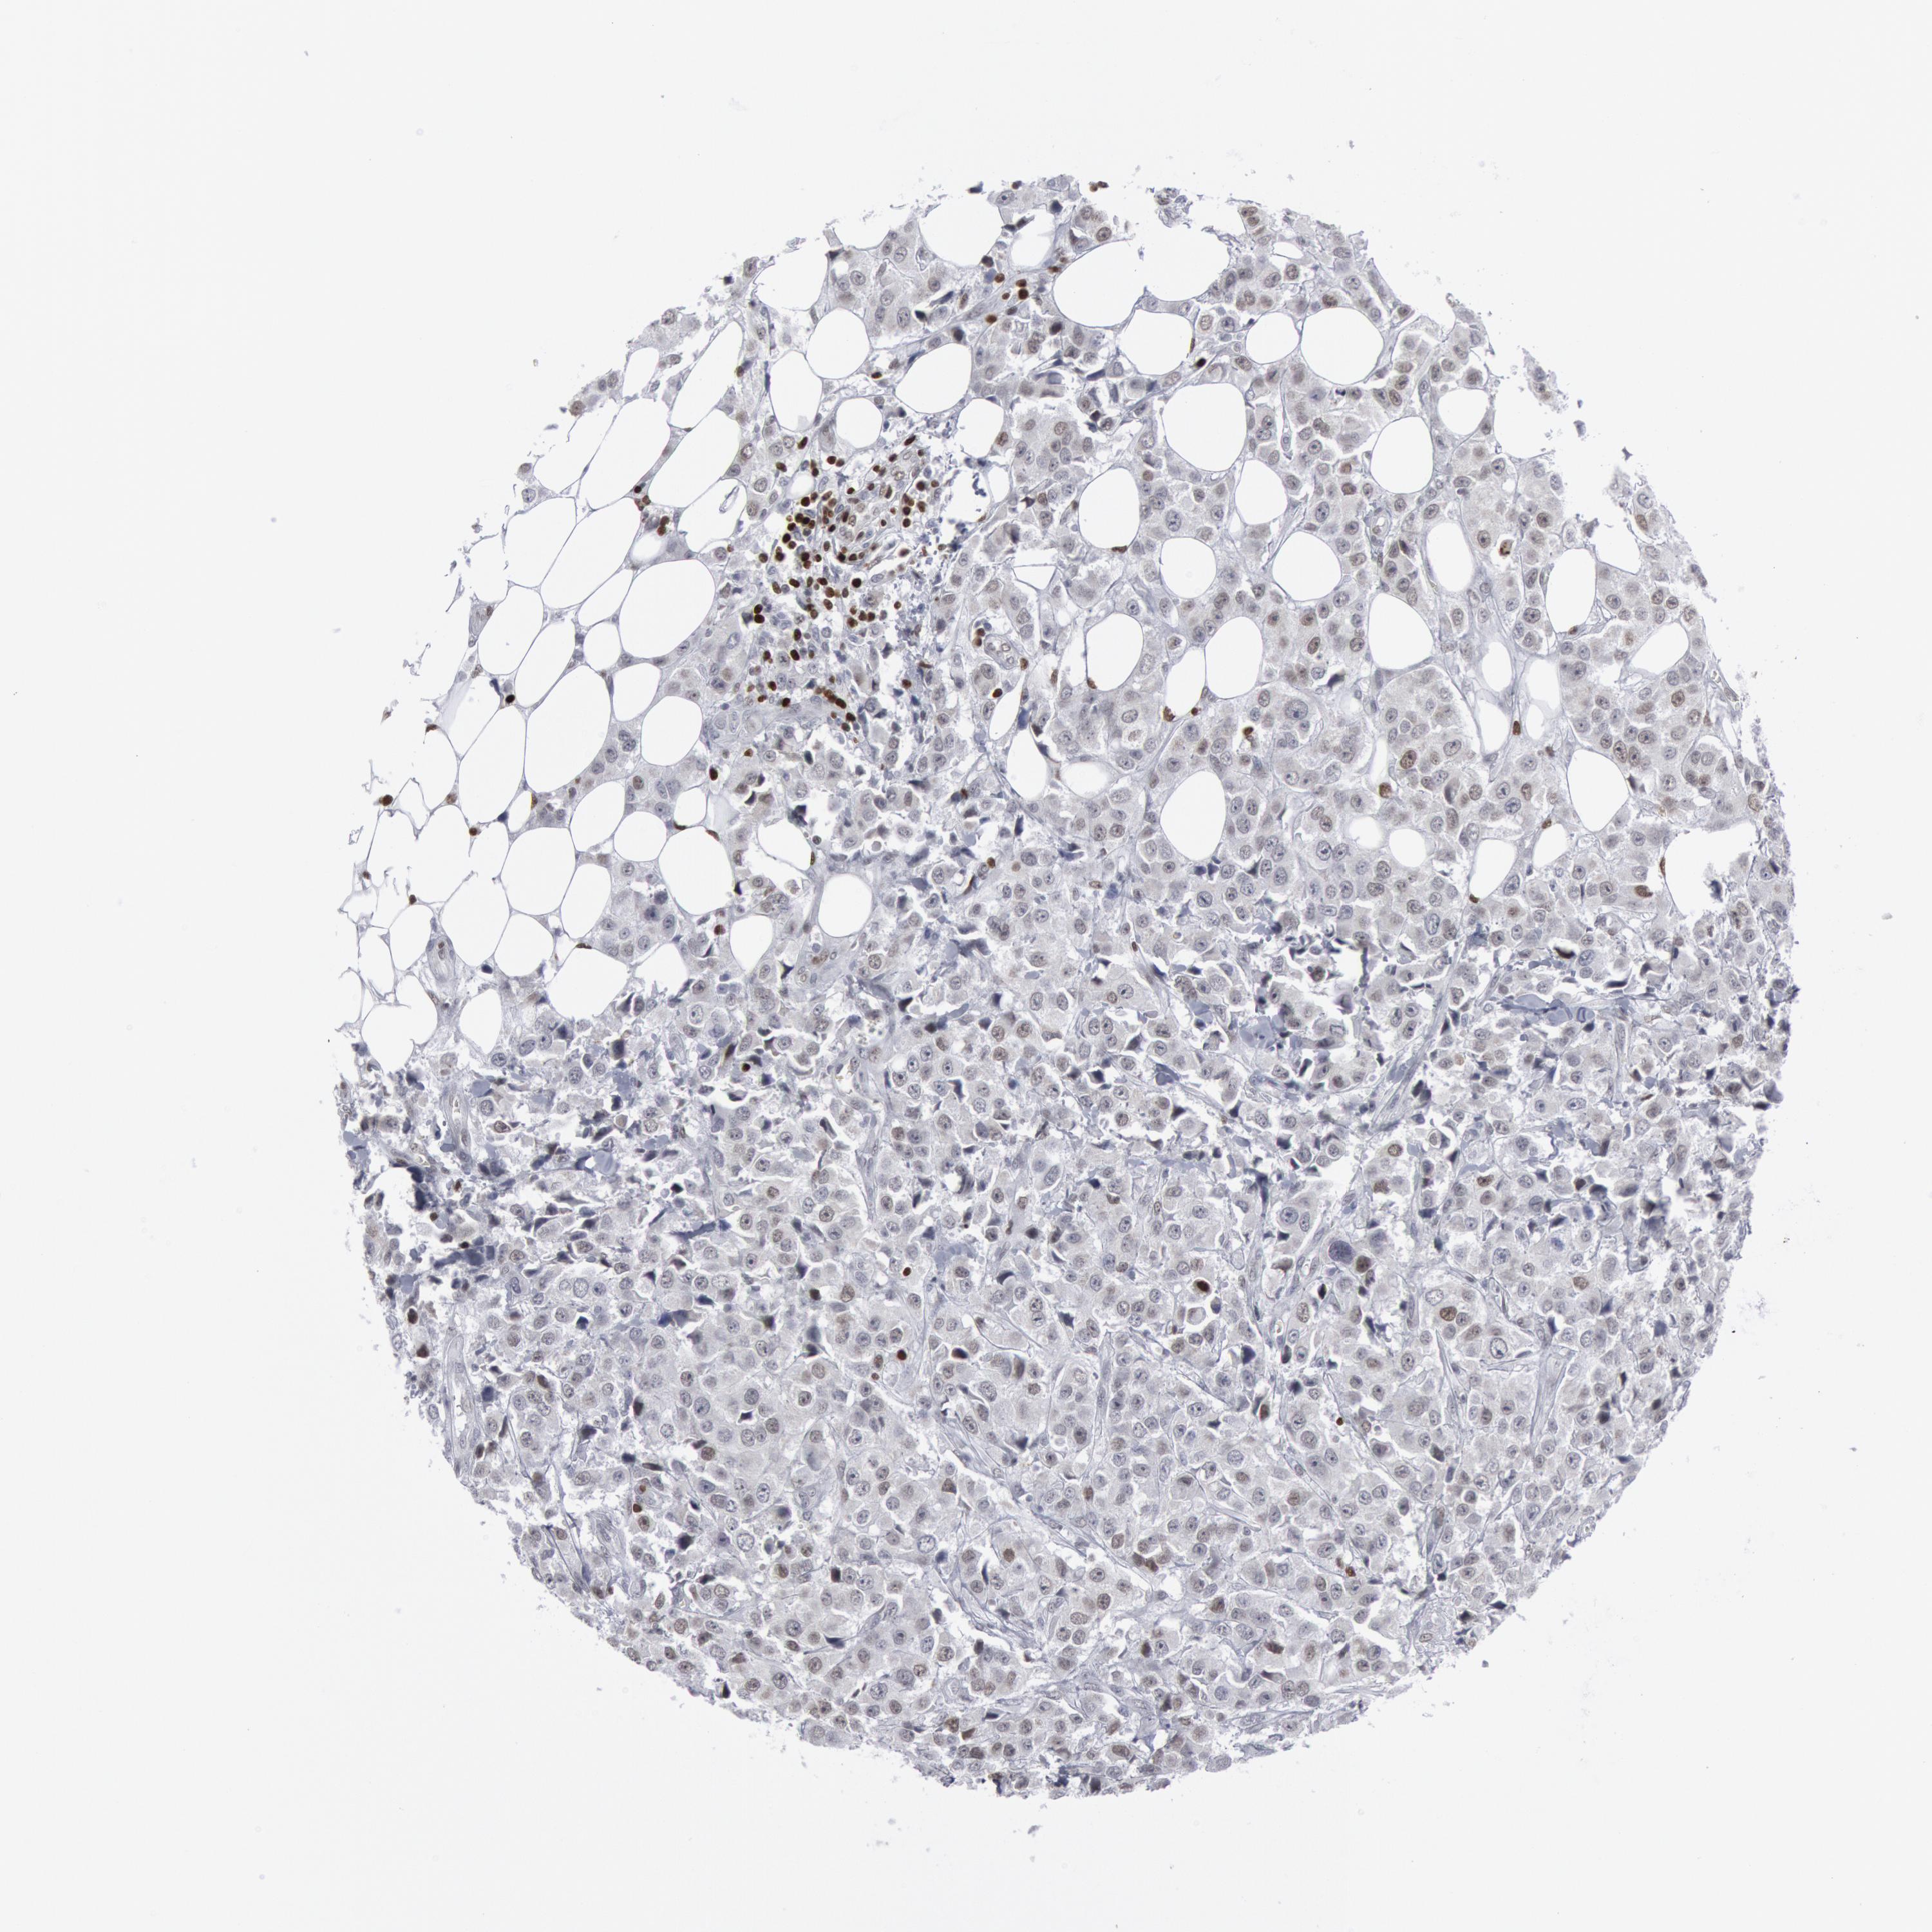

CANCER BREAST CANCER Show tissue menu

BRCA TCGA BRCA VALIDATION PROTEIN EXPRESSION

ANTIBODIES

AND

VALIDATION